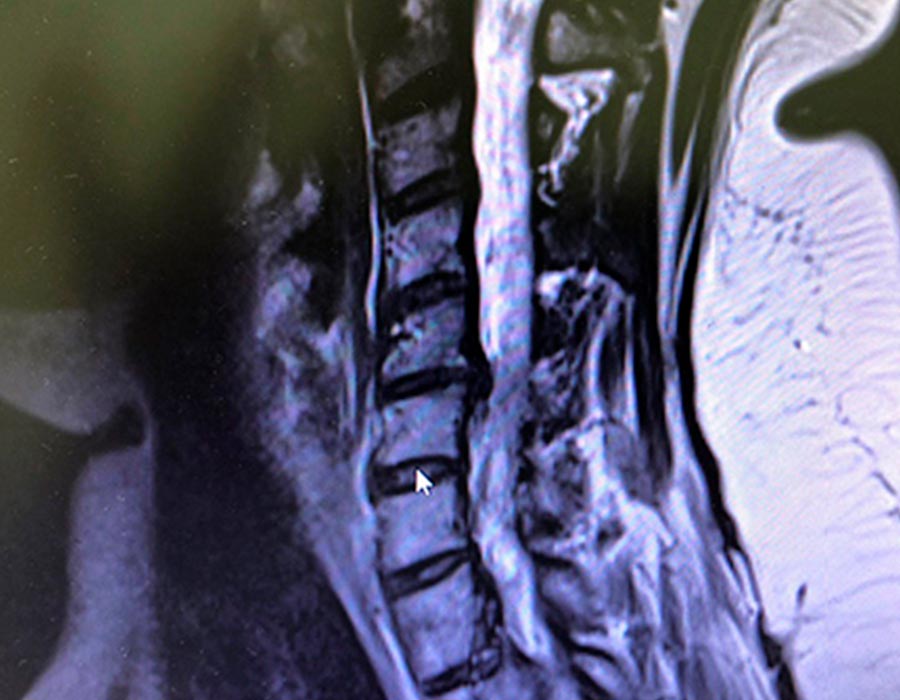

Hoy os presentamos el caso de una paciente de 48 años de edad con una hernia discal izquierda compresiva.

Preoperatorio

Este dolor le condicina al paciente una pérdida de fuerza en el brazo izquierdo así como dolor intenso por el brazo y hombro. Tras tratamiento médico y rehabilitador sin éxito, comento a la paciente que requiere una cirugía mínimamente invasiva para solucionarle el problema.

Hernia discal cirugia

Hernia discal cuello